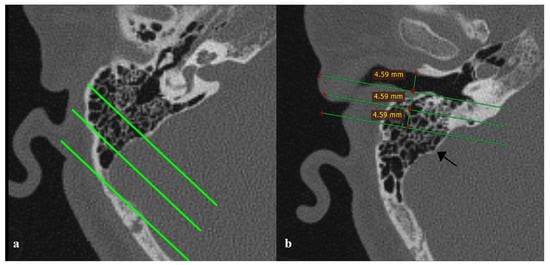

The Possible Relationship Between Sigmoid Dehiscence, Degree of Mastoid Pneumatization, and Sigmoid Sinus Position in Patients with Pulsatile Tinnitus

Objective: This study aimed to determine the relationship between sigmoid sinus dehiscence (SSD), sigmoid sinus topography, mastoid pneumatization, and adjacent temporal bone structures in patients with pulsatile tinnitus (PT). Methods: A retrospective analysis was performed on 344 temporal bone cone-beam computed tomography (CBCT) scans (172 PT patients and 172 age- and sex-matched controls). The degree of mastoid pneumatization, presence and size of SSD, sinus topography, and distances between the sigmoid sinus and key landmarks—the lateral semicircular canal (LSCC), jugular bulb (HJB), and external auditory canal (EAC)—were measured. Quantitative and qualitative characteristics were compared between groups, and independent predictors of PT were identified using multivariate logistic regression. Results: Compared to controls, SSD was substantially more common in the PT group (115/172 vs. 44/172, p < 0.001). Patients with PT had significantly larger anteroposterior and vertical sigmoid sinus dehiscence diameters (4.61 ± 0.99 mm vs. 3.87 ± 0.25 mm and 3.37 ± 0.47 mm vs. 2.92 ± 0.14 mm, respectively; both p < 0.01). Additionally, in the PT group, the sigmoid sinus was situated closer to the lateral semicircular canal, jugular bulb (JB), and external auditory canal (all p < 0.01). Conclusions: Venous pulsatile tinnitus was substantially correlated with sigmoid sinus dehiscence, sinus topography, and decreased sinus–EAC distance. Quantitative CBCT evaluation of these anatomical relationships could help with surgical planning and enhance diagnostic evaluation. Full article